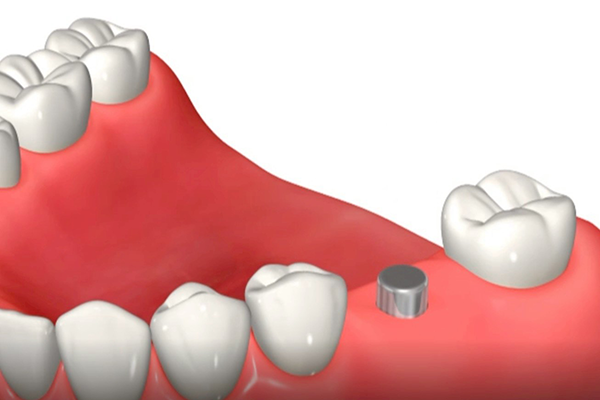

埋入直後のインプラント体と周囲骨との間の嵌合力により得られる機械的な固定を初期固定と言います。初期固定は、インプラント体の形状、骨質や骨量、手術術式、などに影響されます。一方、埋入後の骨治癒が進行してインプラント体が安定してくる生物学的固定を二次固定といいます。

この画像のように、埋入直後はインプラント体と骨の間は機械的な固定があるのみですが、段々と時間が経ち治癒が進行してくると、しっかりとした二次固定が得られるようになります。